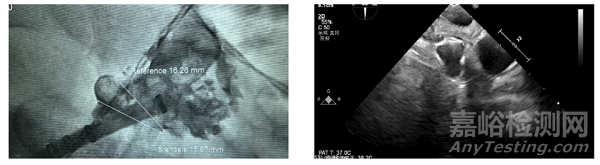

左心耳解剖:DSA 造影顯示心耳為 “前后雙分葉” 形態(tài),共干區(qū)域深度僅 16.2mm(淺心耳),遠(yuǎn)端分葉無(wú)法利用,口徑 22mm—— 淺心耳的挑戰(zhàn)在于封堵器 “錨定空間不足”,易出現(xiàn)術(shù)后移位。

2. 手術(shù)操作過(guò)程

器械選擇:選用27mm 規(guī)格 WATCHMAN FLX Pro,利用器械的 “徑向支撐力” 確保在淺心耳內(nèi)的錨定穩(wěn)定性。

定位與評(píng)估:通過(guò)RO Marker 確認(rèn)封堵器完全覆蓋共干區(qū)域,避免遠(yuǎn)端分葉遺漏;術(shù)后 TEE 顯示封堵器無(wú)移位,瓣周漏<2mm,符合 PASS 原則。

全球首款,波科涂層左心耳封堵器獲批上市

▲術(shù)前左心耳造影(左);封堵器展開(kāi)后造影(右)

3. 術(shù)后專家反饋

馬長(zhǎng)生教授在術(shù)后訪談中強(qiáng)調(diào)(來(lái)源2):“我們臨床中常遇到高齡、合并多基礎(chǔ)疾病的患者,他們服用抗凝藥的出血風(fēng)險(xiǎn)遠(yuǎn)高于卒中預(yù)防獲益。WATCHMAN FLX Pro 的 PVDF-HFP 涂層能加速內(nèi)皮化,理論上可將抗凝用藥時(shí)間從傳統(tǒng)的 6 個(gè)月縮短至 1-3 個(gè)月,這對(duì)高出血風(fēng)險(xiǎn)患者是‘雪中送炭’,但具體用藥時(shí)長(zhǎng)還需更多中國(guó)人群數(shù)據(jù)支撐。”